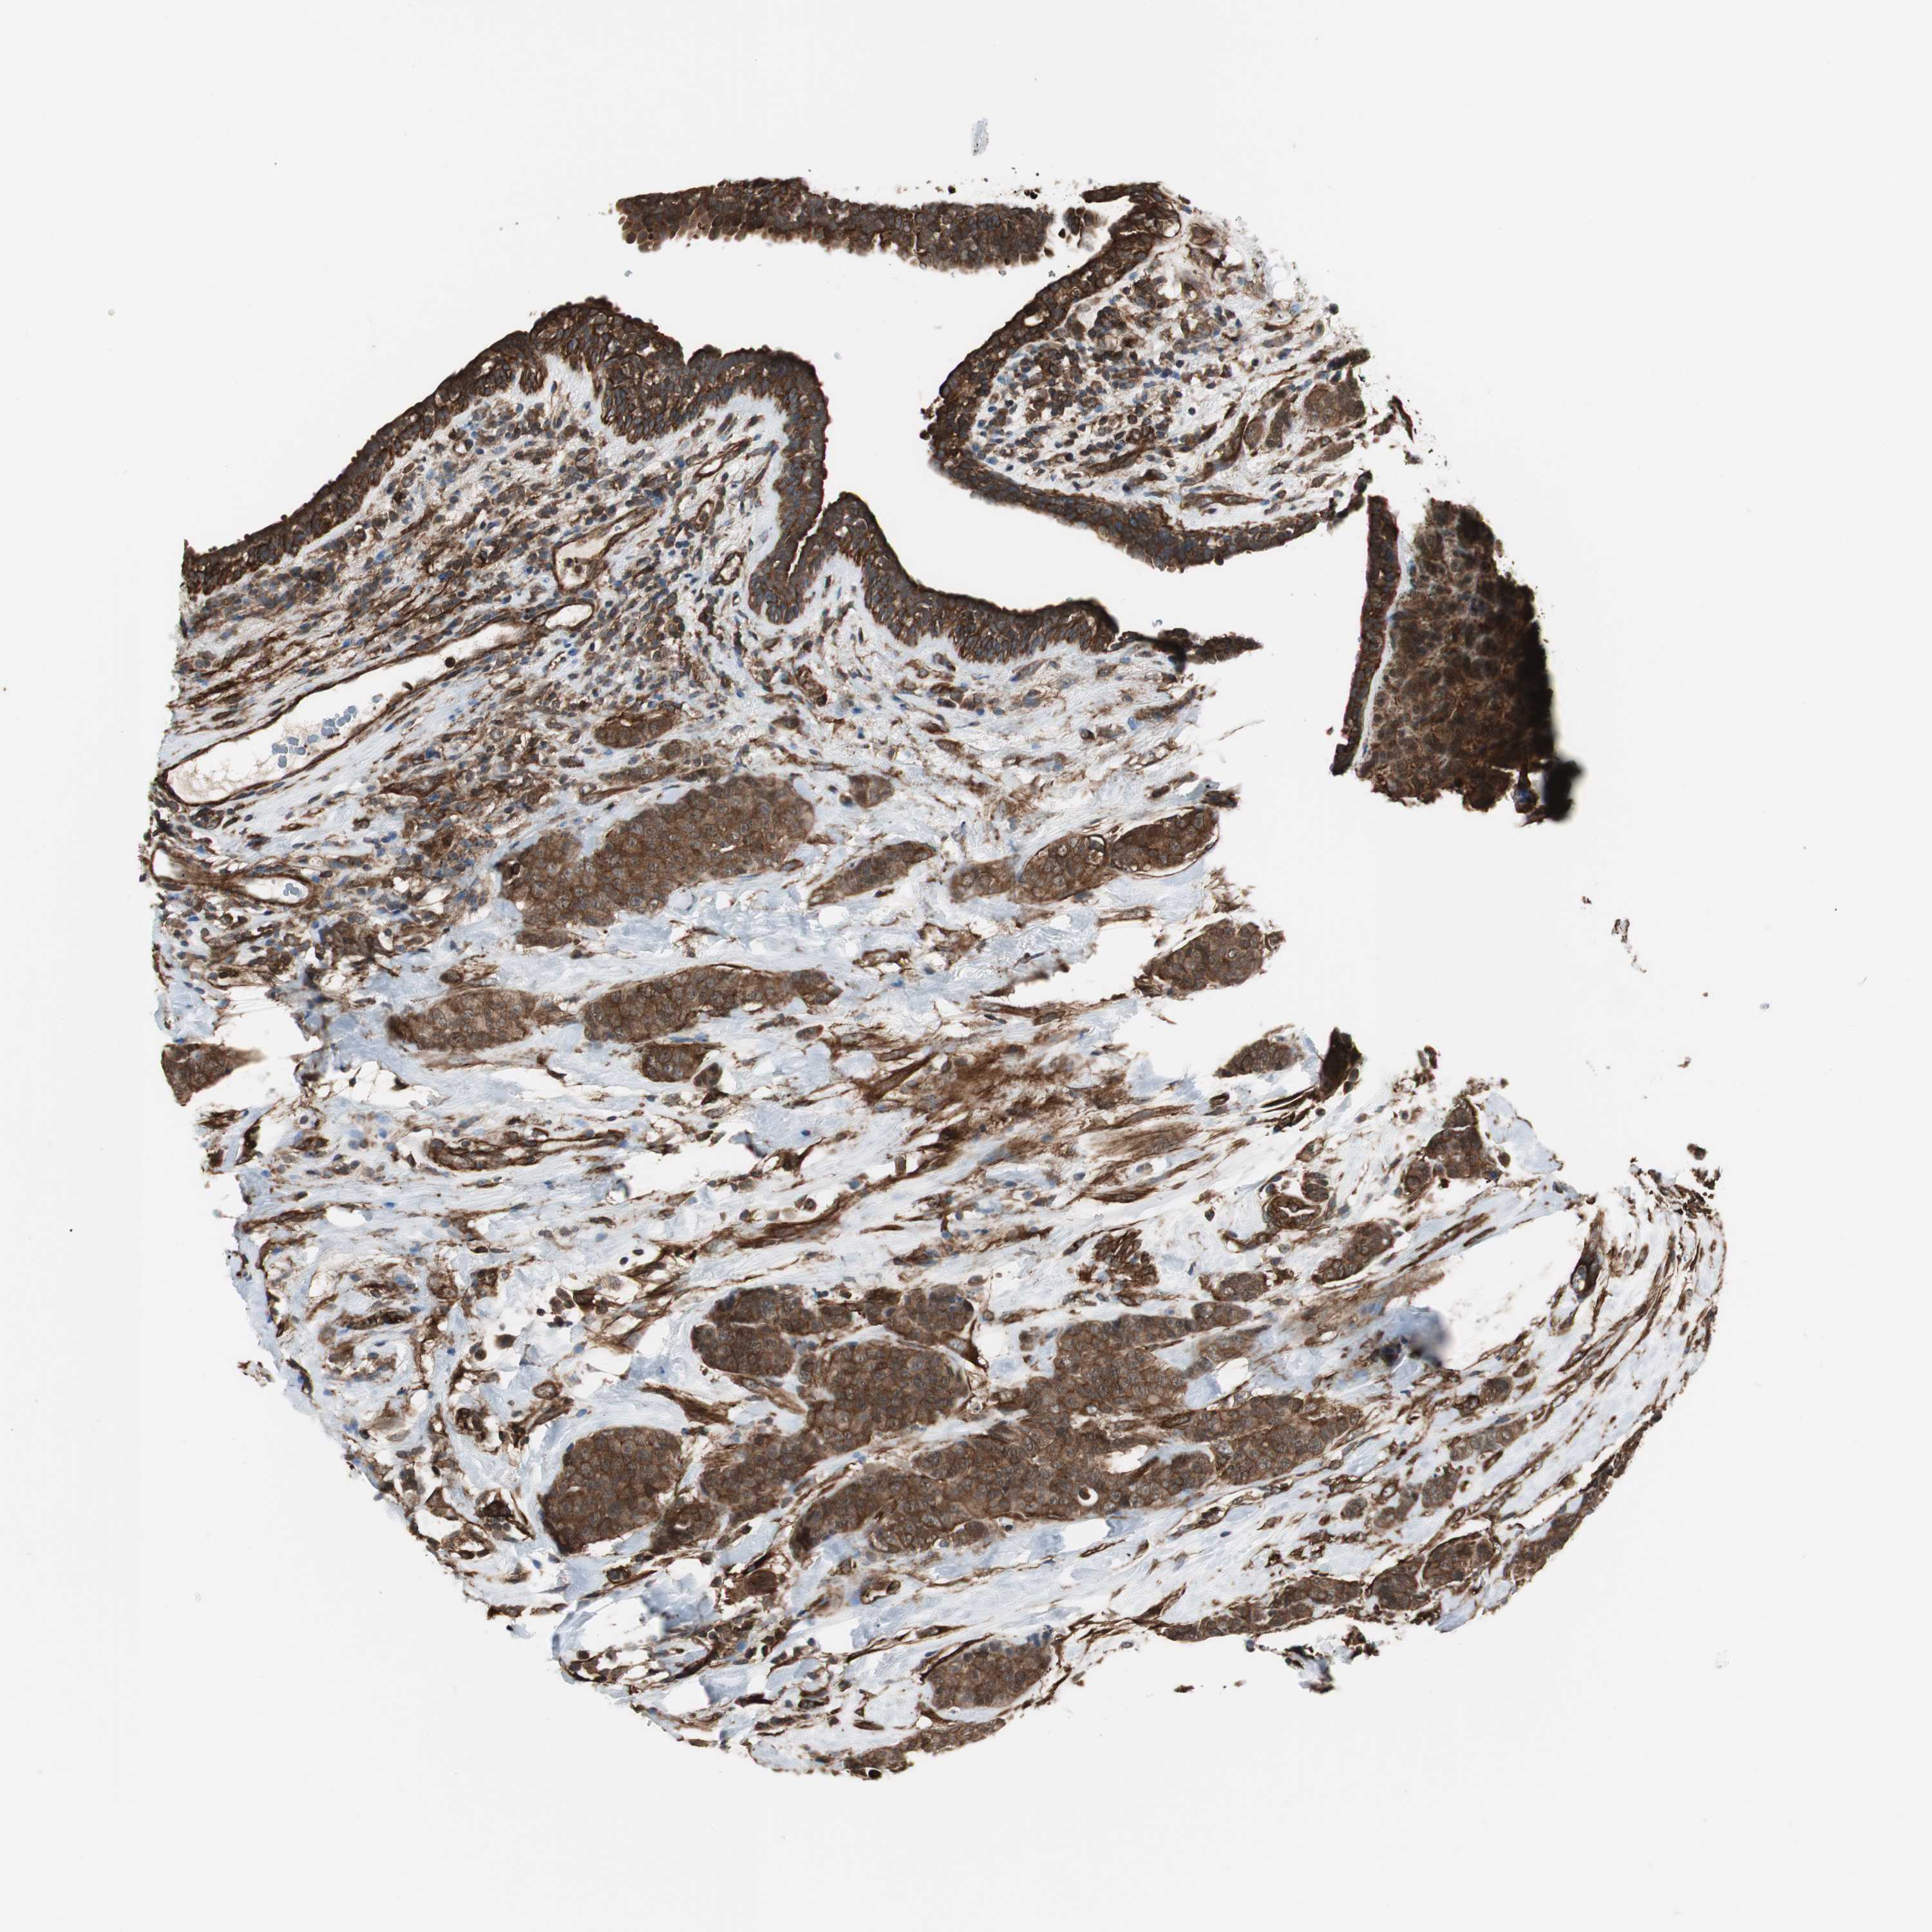

BRCA TCGA BRCA VALIDATION PROTEIN EXPRESSION

ANTIBODIES

AND

VALIDATION